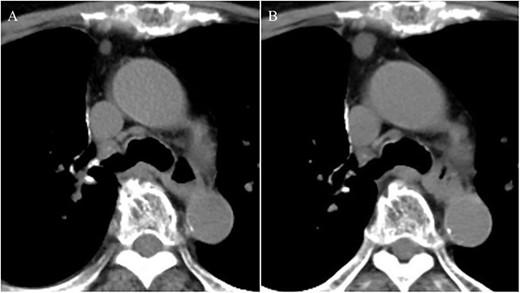

An 81-year-old woman was referred to our hospital because of right lung cancer. She underwent right upper lobectomy by video-assisted thoracic surgery. Pathological examination revealed stage 1A adenocarcinoma. Four months postoperatively, chest computed tomography showed a small nodule with a diameter of 6 mm at the anterior mediastinum (Fig. 1A). After 2 years, the nodule had increased to 13 mm (Fig. 1B). Chest magnetic resonance imaging showed a mediastinal tumor with low-signal intensity on T1-weighted images and high-signal intensity on T2-weighted images, and it was diagnosed as a cystic tumor. For diagnosis and treatment, we resected the tumor and surrounding thymic tissue by a left robotic thoracic approach, considering the adhesion in the right thoracic cavity after right pulmonary resection. The operating time was 43 min, and the blood loss volume was 5 ml. The patient had a favorable postoperative course and was discharged 3 days after surgery. Pathological examination revealed a thymic cyst and microscopic thymoma with a diameter of 400 μm very close to the thymic cyst (Fig. 2).

Chest computed tomography showing a small nodule with a diameter of 6 mm at the anterior mediastinum (A); after 2 years, the nodule had enlarged to 13 mm (B).